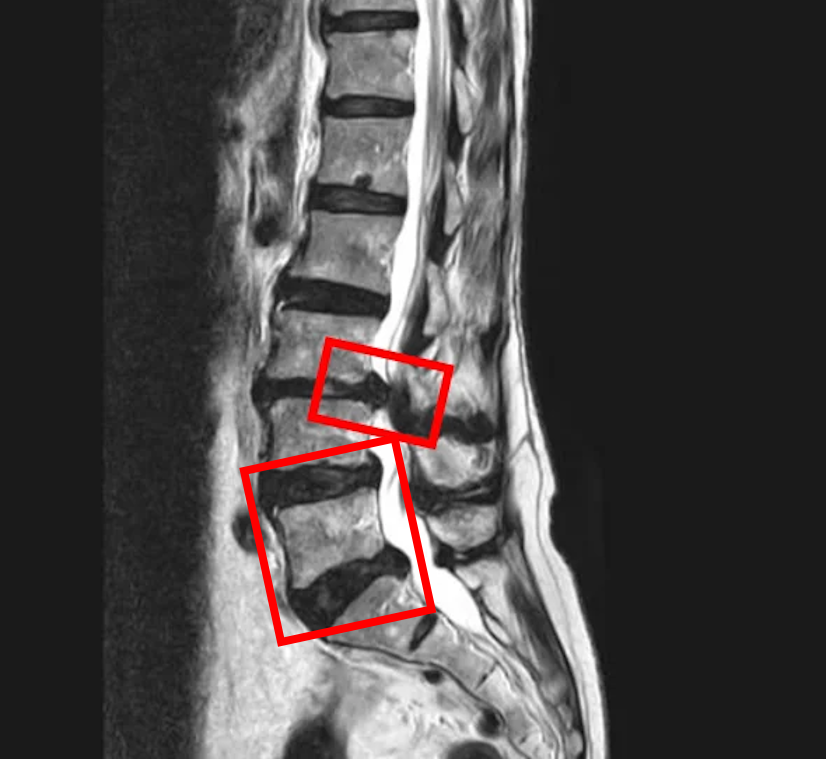

По данным МРТ и результатам осмотра пациентки выявлены стеноз позвоночного канала, вызванный межпозвоночной грыжей диска L3/L4, а также дегенерация межпозвоночных дисков L4/L5 и L5/S1.

В клинике проведена селлгель-терапия на 3 межпозвоночных дисках (L3/L4, L4/L5, L5/S1).